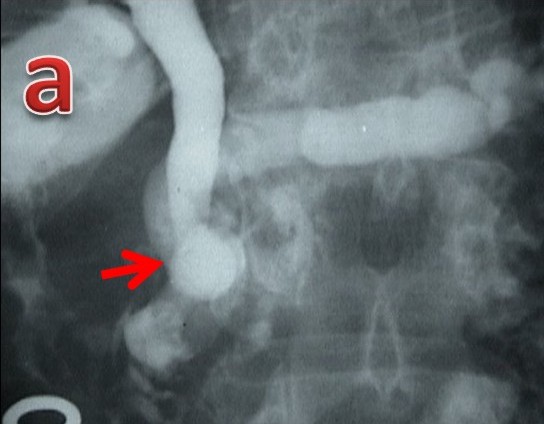

The distribution of pancreaticobiliary ductal union in 174 control group patients with no pancreaticobiliary disease was as follows: separate opening in 86 (49.4%), a short common channel in 50 (28.7%), a long common channel in 32 (18.4%) and anomalous pancreaticobiliary ductal union in 6 (3.4%). In contrast to the control group, the distribution of pancreaticobiliary ductal union in the 21 patients with tropical calcific pancreatitis was as follows: separate opening in 5 (23.8%; P=0.036; OR=0.32, 95% CI: 0.11-0.91), a short common channel in 1 (4.8%; P=0.017; OR=0.12, 95% CI: 0.02-0.95), a long common channel in 7 (33.3%; P=0.144; OR=2.22, 95% CI: 0.83-5.94) and anomalous pancreaticobiliary ductal union in 8 (38.1%; P<0.001; OR=17.2, 95% CI: 5.19-57.2) (Table 2). The data suggest that separate openings and a short common channel were less often seen in tropical calcific pancreatitis as compared to the control group and a long common channel and anomalous pancreaticobiliary ductal union were more often seen in tropical calcific pancreatitis patients as compared to the control group. The type of anomalous pancreaticobiliary ductal union in the 2 groups was different: 6 (75.0%) of the 8 patients with tropical calcific pancreatitis had the B-P type of anomalous union in contrast to the control group in whom five (83.3%) of the 6 patients had the P-B type of anomalous union (P=0.103; OR=15.0, 95% CI: 1.03-218). The bile duct had joined the pancreatic duct in the neck region in one, the body region in 4 and the distal body/tail region in one patient (Figure 5). The angle of union of the anomalous pancreaticobiliary ductal union was also significantly different in tropical calcific pancreatitis patients (88.1±36.2°) than in control group (20.0±11.5°) (P<0.001). Patients with tropical calcific pancreatitis had significantly (P<0.001) longer anomalous channels (26.6±12.2 mm) than did those in the control group (19.6±6.1 mm).

|

Figure 5. Tropical calcific pancreatitis. a. ERCP image showing a grossly dilated pancreatic duct with filling defects in the side branches and a dilated bile duct joining it in the pancreatic neck region (arrow) to form anomalous pancreaticobiliary ductal union of the B-P type. b. ERCP image showing a grossly dilated pancreatic duct with multiple large filling defects and the bile duct joining it in the body region (arrow) to form anomalous pancreaticobiliary ductal union of the B-P type. c. ERCP image showing a grossly dilated pancreatic duct with filling defects in the side branches and the bile duct joining it in the distal body region (arrow) to form a very long anomalous pancreaticobiliary ductal union of the B-P type. |